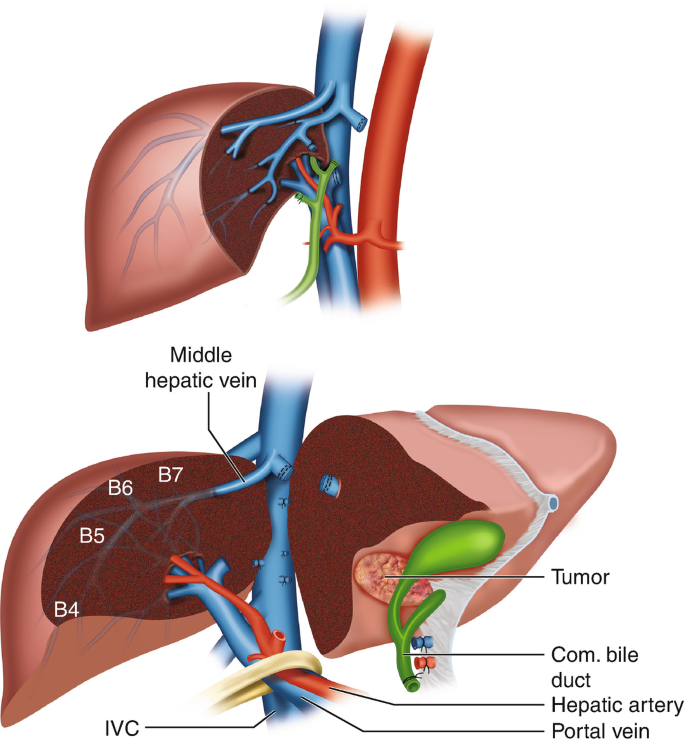

Left hepatectomy is a surgical procedure in which the left lobe of the liver (segments II, III, and IV) is removed. It is commonly performed to treat liver tumors, cancers, or complex conditions affecting this portion of the liver. Since the liver has a natural ability to regenerate, the remaining right side grows and adapts to continue vital functions after surgery.

- Liver tumors or cancers- Tumors confined to the left lobe that can be safely removed.

- Cholangiocarcinoma- Left-sided bile duct cancer requiring tumor clearance.

The left lobe is carefully removed using modern surgical tools to minimize blood loss and protect nearby structures.

Only the diseased portion is taken out, keeping as much healthy liver as possible.